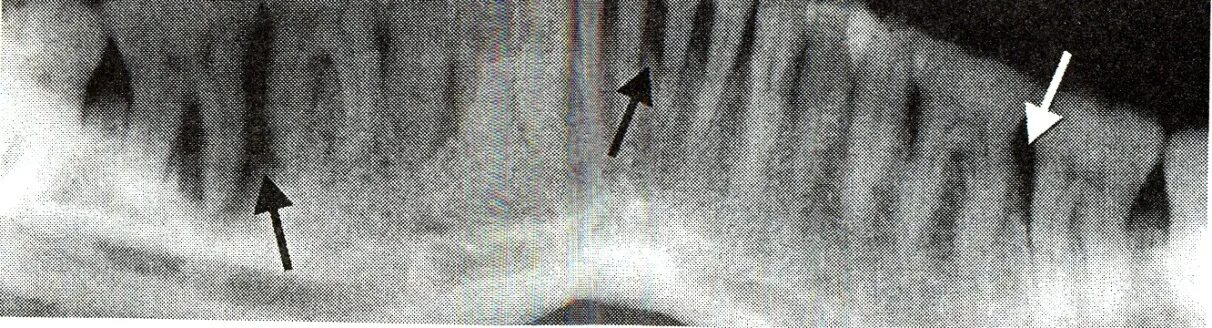

Резорбция ткани